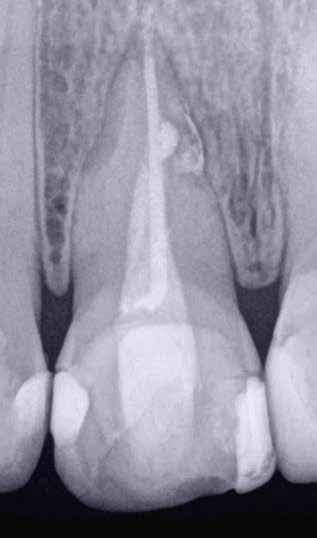

1. a–g. ábrák: A direkt pulpasapkázás lépései. Kiindulási bitewing-felvétel: A meglévő restaurátum közel helyezkedett el a pulpakamrához (a). Kiindulási periapicalis felvétel: Nincs periapicalis elváltozás fennállására utaló jel (b). A pulpaexpozíció (c). A vérzéscsillapítás céljából 20 másodpercen keresztül steril vattagombóccal történő kompressziót követően látható pulpaseb (d). A pulpasapkázás céljából behelyezett anyag, a széli részek tisztázása előtt készült felvétel (e). A röntgenárnyékot nem adó ideiglenes tömés behelyezése után készült felvétel (f). Az első ülés végén a röntgenárnyékot nem adó ideiglenes töméssel ellátott fogról készített röntgenfelvétel (g).

2. ábra: A hat hónapos kontroll alkalmával készített röntgenfelvételen vastag dentinhíd látható a pulpasapkázó anyag alatt.

3. ábra: A hároméves kontroll alkalmával készített röntgenfelvételen megfigyelhető a restaurátum pontos illeszkedése.

A diagnózisunk reverzibilis pulpitis volt. Periapicalis elváltozás jelenlétét nem vélelmeztük. A fogban lévő amalgámtömés eltávolítása során körülbelül egy 3 mm átmérőjű pulpaseb keletkezett a buccalis pulpaszarvnak megfelelően (1. a–g. ábrák) Mivel nem tapasztaltunk jelentős vérzést, és a diagnózisunk reverzibils pulpitis volt, ezért a direkt pulpasapkázás elvégzése mellett döntöttünk.

A kezelést követően a beteg tünetmentes volt. A kérdéses fog a kontrollvizsgálatok során végzett szenzibilitástesztekre fiziológiás reakciókat adott. A hat hónapos kontroll alkalmával készített röntgenfelvételen a sérülésnek megfelelően széles dentinhidat észleltünk (2. ábra). A restaurátum a hároméves kontroll során is megfelelőnek bizonyult (3. ábra)